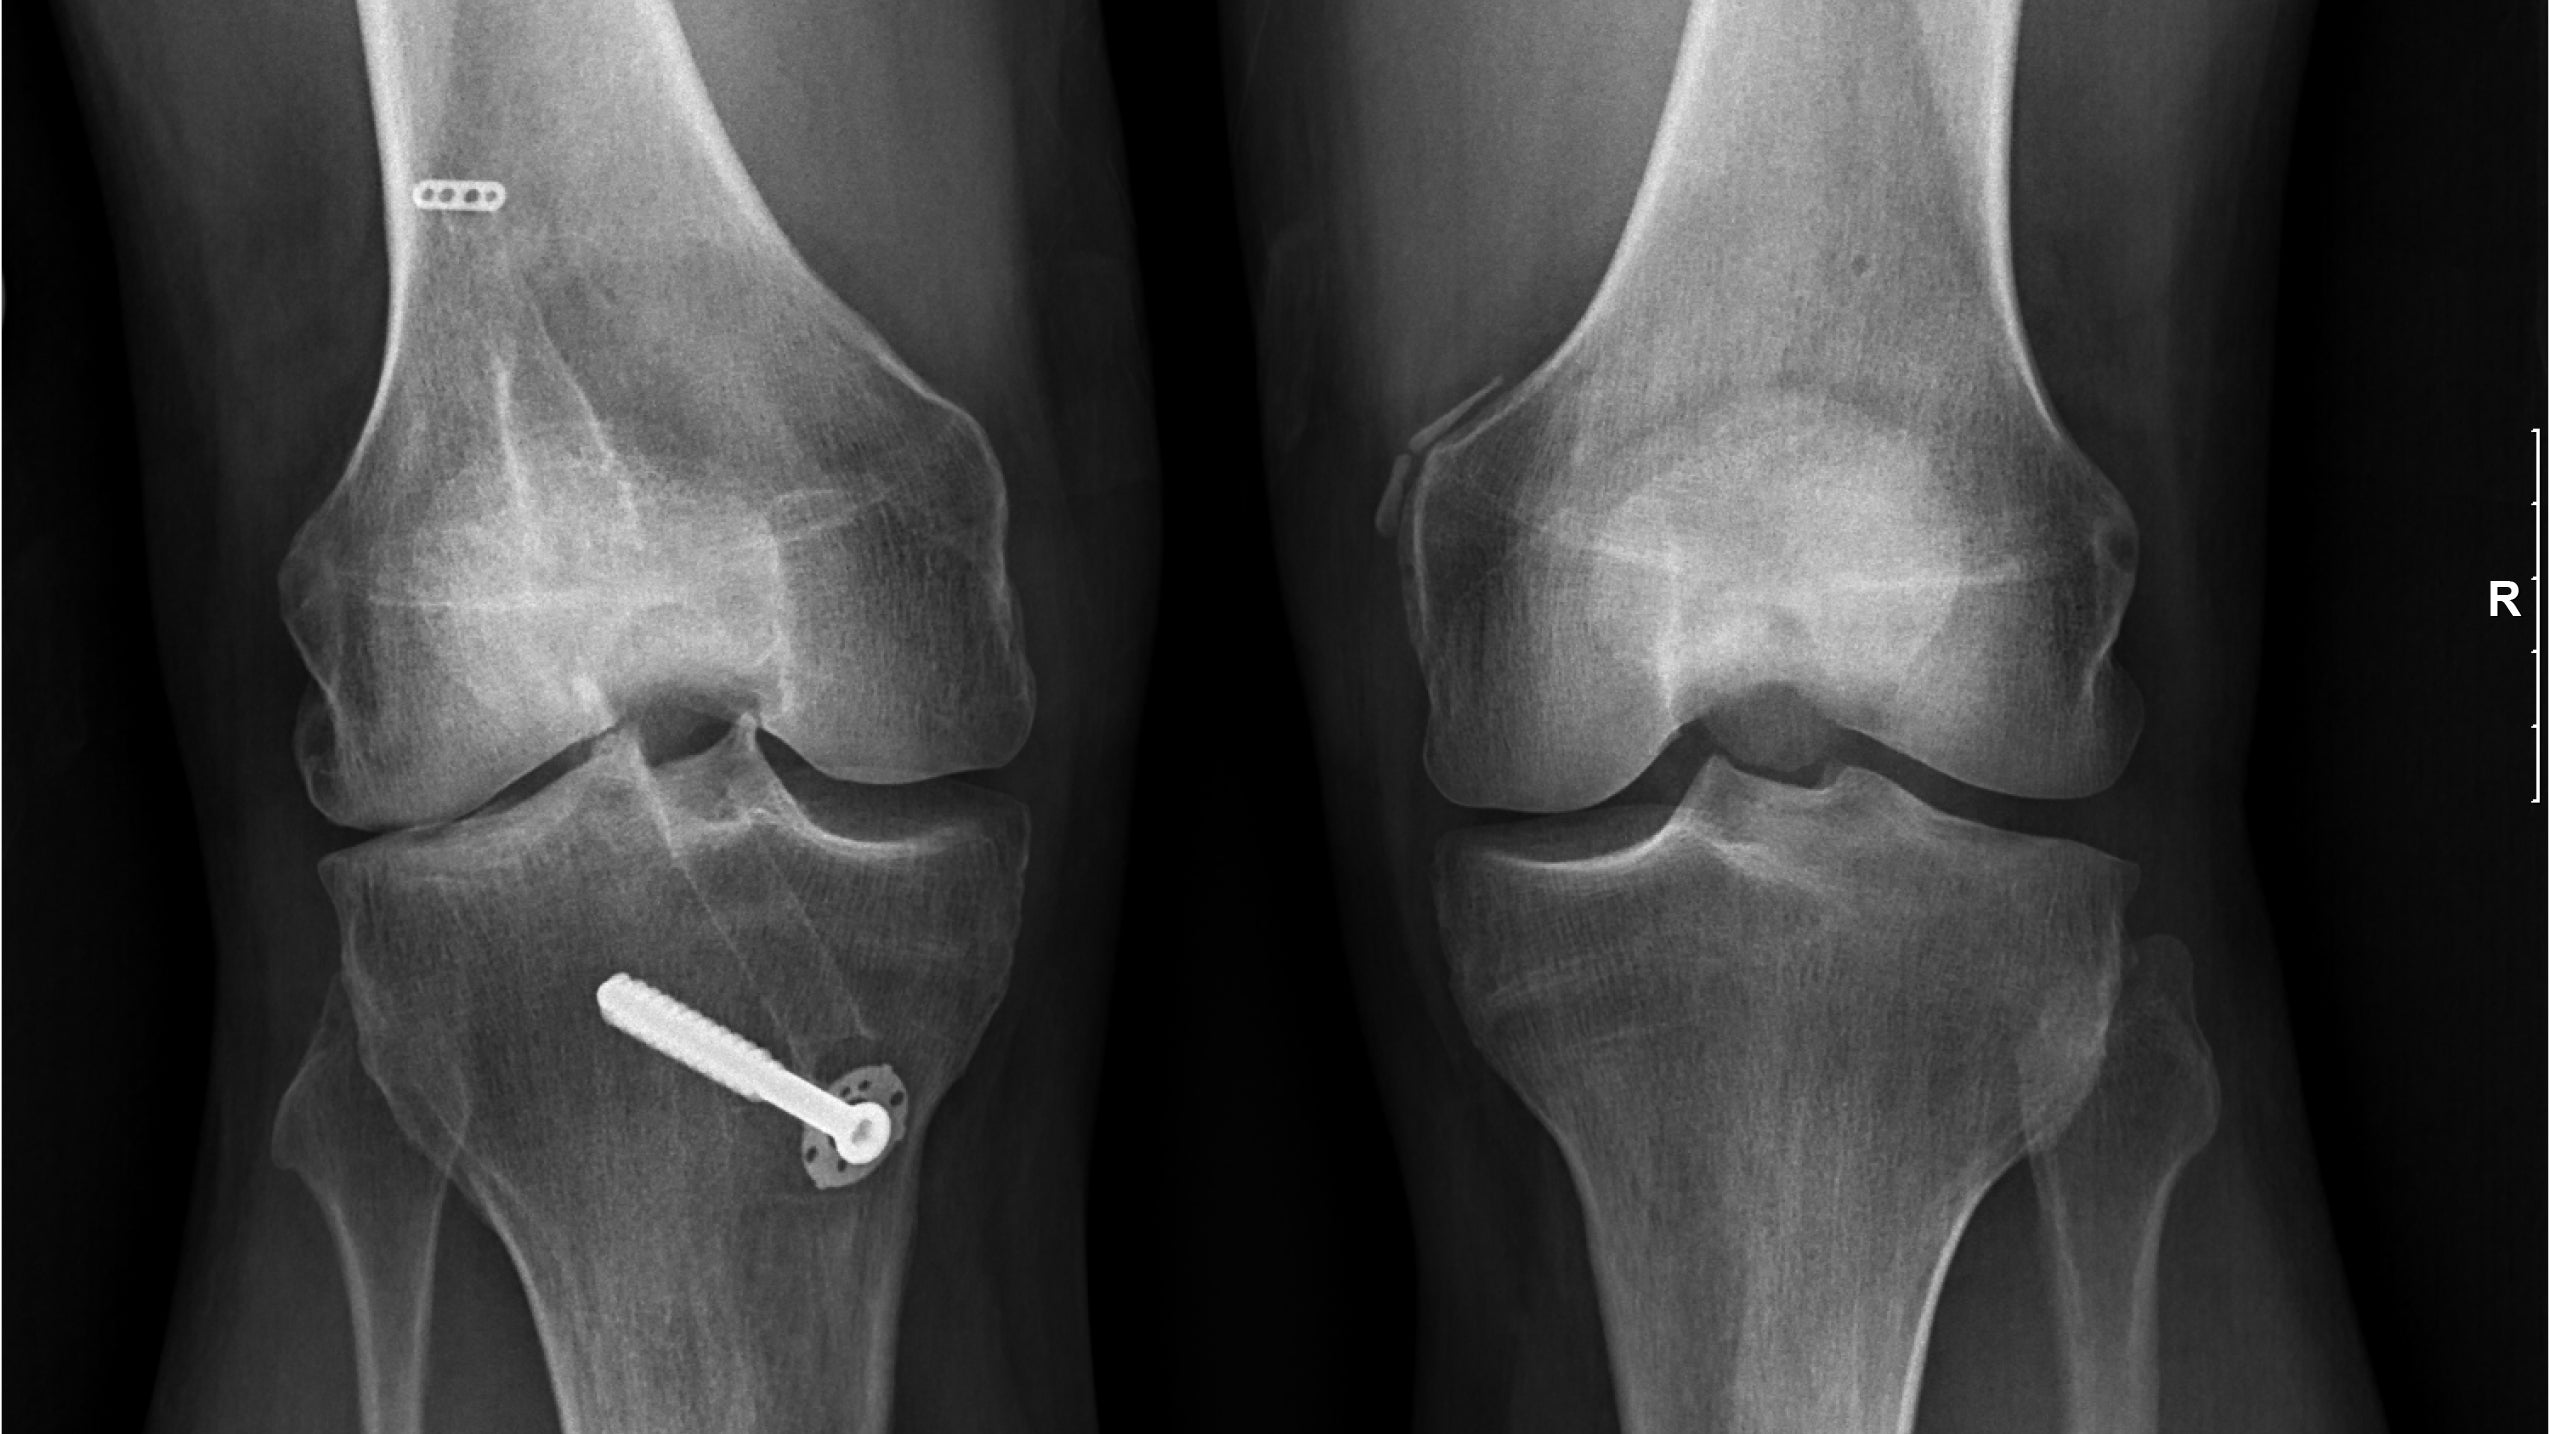

(Photo: Courtesy of Petrick)

But in 2000, one of a skier’s worst fears struck while Petrick was heli skiing in Alaska. “I tumbled down a couloir following (the late) Doug Coombs in deep powder and blew my ACL out,” says Petrick. “I also lost parts of my medial and lateral meniscus from going end over end.” After surgery to repair his ACL, his knee deteriorated over the next decade, and he was prescribed an unloader knee brace, which mitigated the pain just enough so he could ski. “I wore that brace religiously because if I didn’t wear it, my knee would ache like crazy,” he says.

His doctor, Mark D. Wagner, MD, of Seattle Sports & Regenerative Medicine, recommended an alternative to the invasive joint replacement surgery. Wagner, an avid skier himself, had recently begun performing a procedure called Stem Cell Therapy. The procedure uses the patient’s stem cells mixed with a bone marrow and adipose tissue sample, which is spun in a centrifuge and injected into the damaged joint in what Wagner likens to spackle filling in the cracks. “You can also think of the stem cells as seeds you put on the bare spots on your lawn,” says Wagner. “Your platelets are the fertilizer, promoting growth. The stem cells sense the environment, go into the joint, and lay down new cartilage.”

The payback many skiers face after years of carving turns down icy slopes or the repetitive pounding from moguls is the breaking down of cartilage in their joints, particularly the knees. Cartilage is the tissue found on all joint surfaces, but because it’s not supplied with blood vessels, it doesn’t self-repair. Stem cells are found throughout the body and have the potential to become any type of cell—including those found in cartilage. They can help the body regenerate tissue by implanting cells that stimulate healing and reduce the painful effects of osteoarthritis. “Our results with Stem Cell Therapy are impressive,” says Wagner. “About 85 percent of patients have significantly improved within one year.”